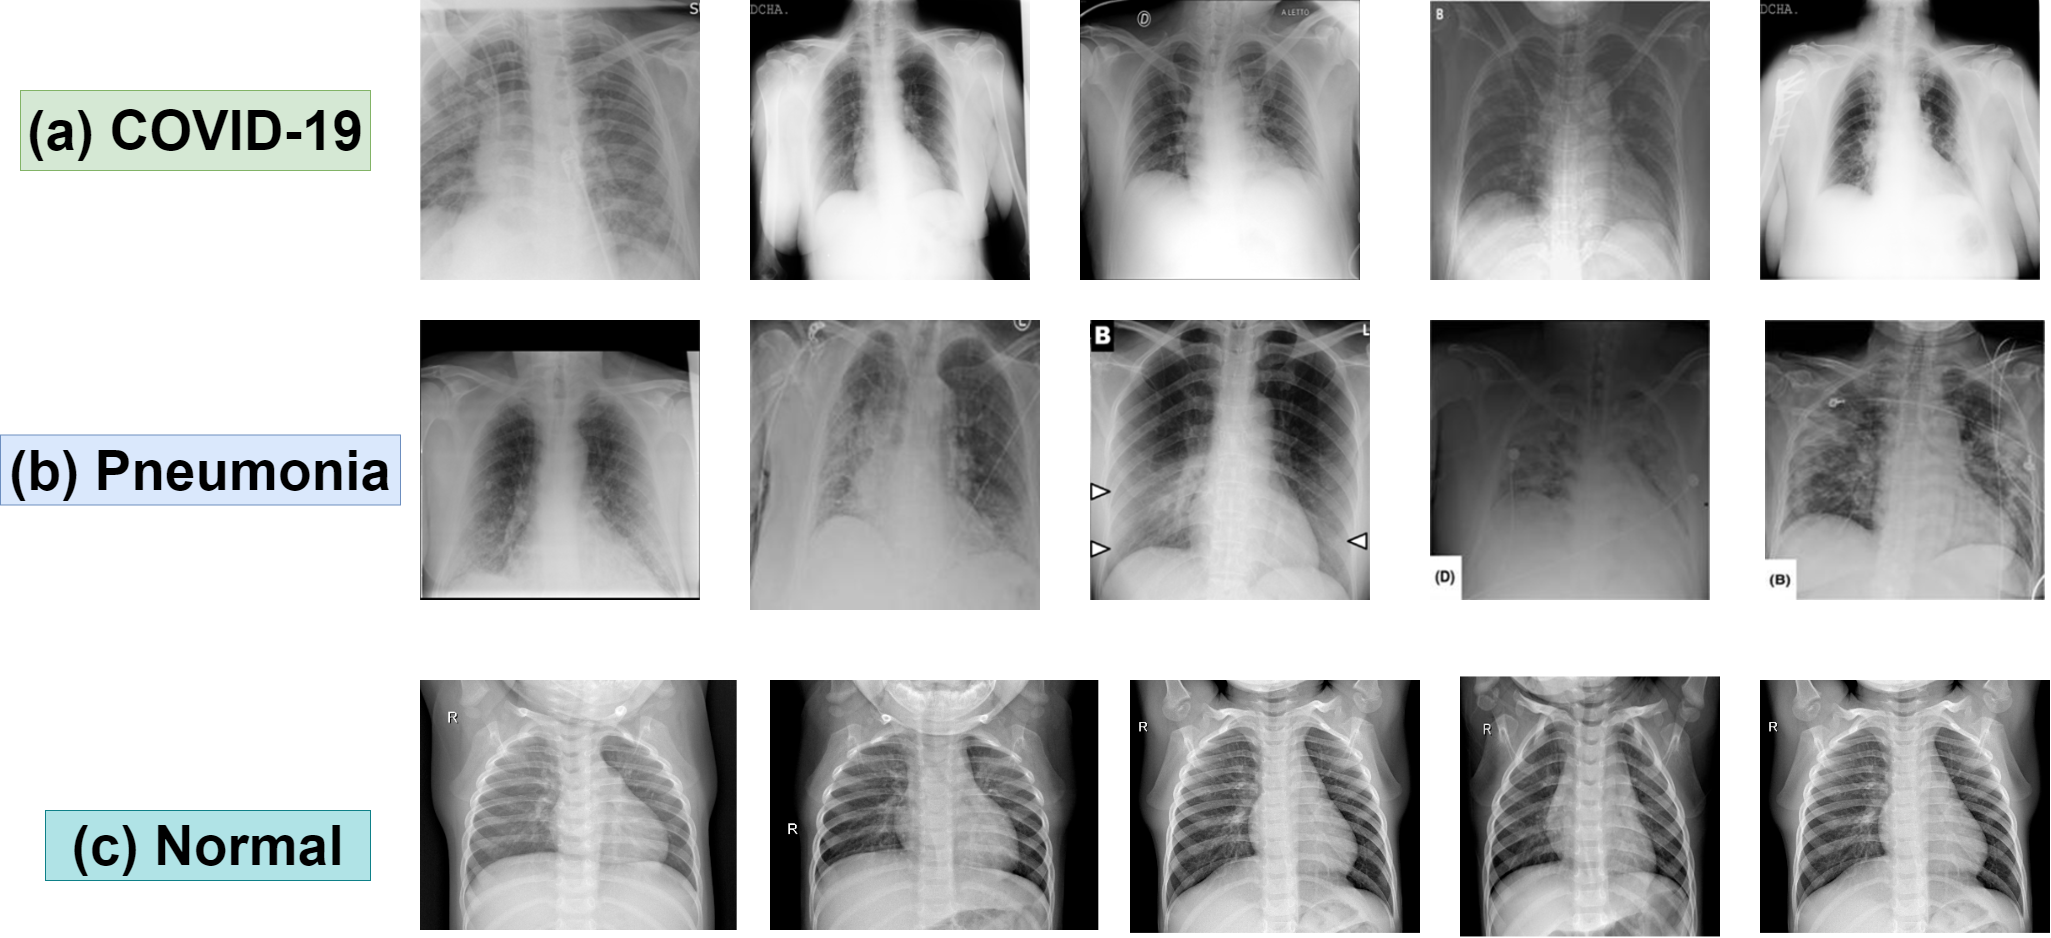

Figure 2: Sample Dataset of (a) COVID-19; (b) Pneumonia; (c) Normal

we processed the image data using the available pre-processing techniques. We have identified corrupted images in the first place. Then, we removed the wrong image data. For example, the X-Ray dataset contains CT-Image data. Then, we figure out the number of images available for the training process and increase the data by the data augmentation process. Next, we used re-scaling, mage-rotation, horizontal-rotation, and zoom-range for the image processing process. We need to split the dataset into two categories known as training sets and testing sets. The train set will do the task of training the dataset and preparing local models for different hospitals. The test set will do the job of testing the predicted diseases. We followed the convention of the training set(80%) and testing set(20%). We will have more accurate results if we can increase the ratio of the training set.